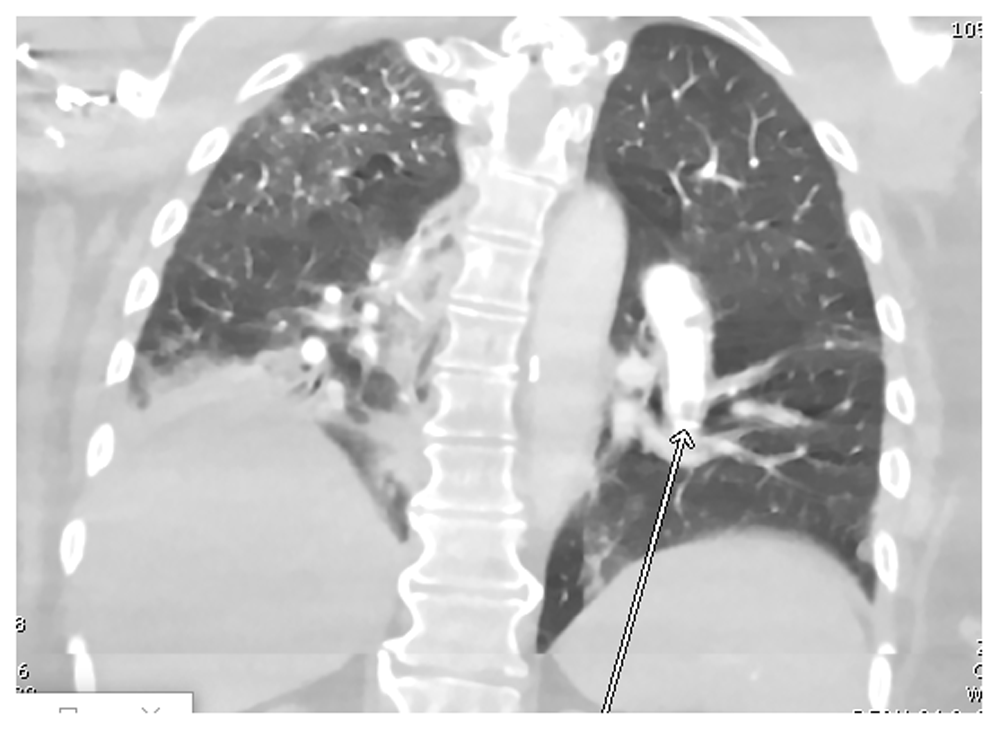

The patient was admitted and started on hydroxychloroquine 400 mg every 12 hours for two doses followed by 200 mg every 12 hours for 5 days in addition to supportive measures, including acetaminophen 650 mg as needed for fever and supplemental oxygen. The patient’s regular hemodialysis schedule was also continued during her admission. A computed tomography pulmonary angiogram Figure 1 revealed pulmonary embolism in the left lower lobe, involving segmental and proximal subsegmental arteries without right heart strain or pulmonary infarction.

Figure 1. CTA chest showing an embolus in a branch of the left pulmonary artery (arrow).